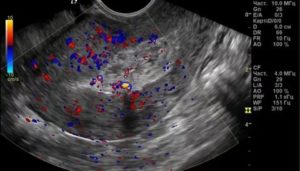

Вагинальное УЗИ зачастую выполняется на ранних сроках беременности. С начала второго триместра такое исследование – не распространенная практика, однако имеет ряд показаний в отдельных случаях. С его помощью можно оценить состояние шейки матки, определить предлежание детского места и т.д.

УЗИ является безопасным, его проводит врач. Заражение через прибор инфекциями исключается, так как на датчик перед вводом надевается специальный презерватив. Заставить делать трансвагинальное УЗИ врач женщину не вправе, однако, именно с помощью данного исследования можно определить внематочное зачатие и другие патологии. Поэтому рекомендуется прислушаться к врачу.

Трансвагинальное УЗИ на ранних сроках

Этот вид исследования на ранних сроках беременности дает более точную картину нахождения плода в матке и состояния половых органов женщины. Процедура проводится быстро. Врач назначает ее по показаниям.

Находясь в утробе, ребенок защищен околоплодными водами и шейкой матки от внешнего воздействия. Поэтому кровь после трансвагинального УЗИ в большинстве случаев просто совпадение.

Гинекологи отдают предпочтение трансвагинальному УЗИ, которое дает четкую картину состояния органов малого таза. Оно может назначаться беременным женщинам, так как помогает проследить за развитием плода, выявить даже незначительные аномалии и определить причину повышенного тонуса живота. Почему предпочтительна именно такая диагностика в каждом случае решает врач.

Преимущество вагинального УЗИ заключается в том, что оно позволяет разглядеть даже мелкие кисты яичника, воспалительные процессы, миомы.

У беременных женщин анализы (мазок) и такое обследование способно дать точную оценку развитию плода. Если присутствует гипертонус, диагностика определяет причину его повышения и помогает принять меры по устранению угрозы.